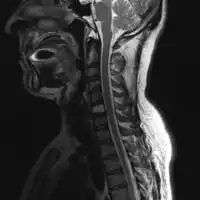

2.a. MRI neck (side view): solitary plasmacytoma C6 -

2.b. MRI neck (view from behind): solitary plasmacytoma C6